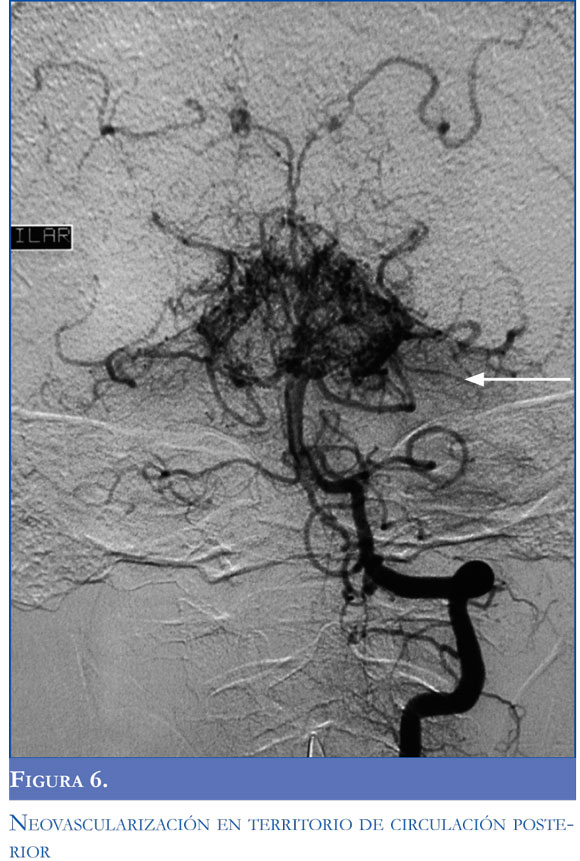

Una arteriografía realizada durante la primera semana de evolución mostró estenosis de la carótida izquierda con adelgazamiento distal de la vascula-tura cerebral con neoformación y colateralización de circulación externa con la interna conformando un patrón típico de síndrome moyamoya (Figuras 3, 4, 5 y 6). El control imagenológico hacia los 15 días de hospitalización evidenció una disminución del 50% en el volumen del sangrado intraventricular. La paciente logró llegar a un alertamiento espontáneo sin contenido de la conciencia ni respuesta al llamado. A los 45 días de evolución logra salir de UCIN con traqueostomía percutánea y nutrición por gastrostomía.

El termino moyamoya fue introducido por Suzuki y Takaku en 1957 por el aspecto angiográ-fico de la circulación colateral cerebral en humo de cigarrillo o fumarola (en japonés "moyamoya"). En esta entidad existe una esteno-oclusión de múltiples vasos intracraneales con aparición de colaterales del polígono de Willis, leptomeningeas o con formación de aneurismas u otras malformaciones arteriovenosas. Cuando existen colaterales entre circulación anterior y posterior o entre la circulación intracraneana y la extracraneana existe mayor riesgo de hemorragia intracraneana. En la enfermedad de moyamoya existe predisposición genética, en cambio, en aquellos pacientes sin la enfermedad pero con el patrón angiográfico típico existe una enfermedad de base (síndrome de moyamoya) que los predispone a desarrollar el daño vascular, como la ateroesclero-sis en ancianos, la neurofibromatosis, la esclerosis tuberosa, la tuberculosis, el síndrome de Down y la enfermedad de células falciformes (5-6). Dobson describió 44 pacientes con enfermedad de células falciformes y demostró que aquellos con síndrome o patrón angiográfico de moyamoya tuvieron más riesgo de eventos cerebrovasculares recurrentes (7).